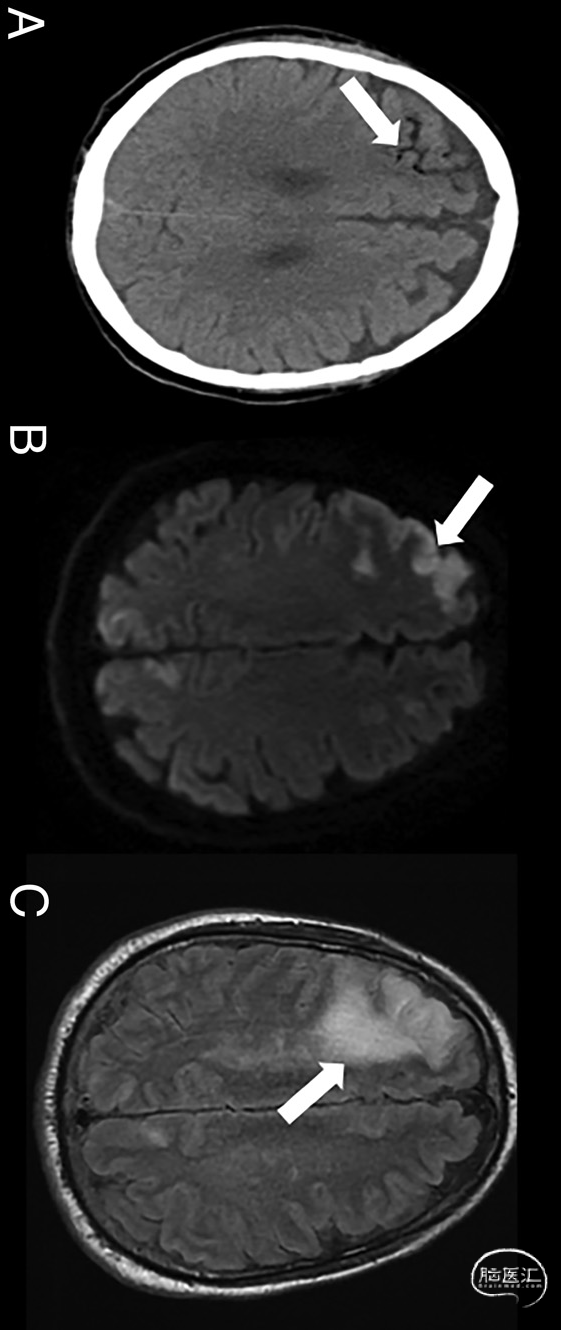

图4.男性,64岁,疑似CAE。平扫脑部CT显示右额叶存在轴外气体(白色箭头,A)。平扫脑MRI显示,双侧(右侧明显)MCA-ACA交界区存在细胞毒性(白色箭头,DWI序列,B)和血管源性水肿(白箭头,T2-FLAIR序列,C)的混合模式。病因为伤口填塞过程中沿患者胸壁腔血管内引入气体: